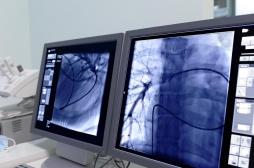

LES MALADIES